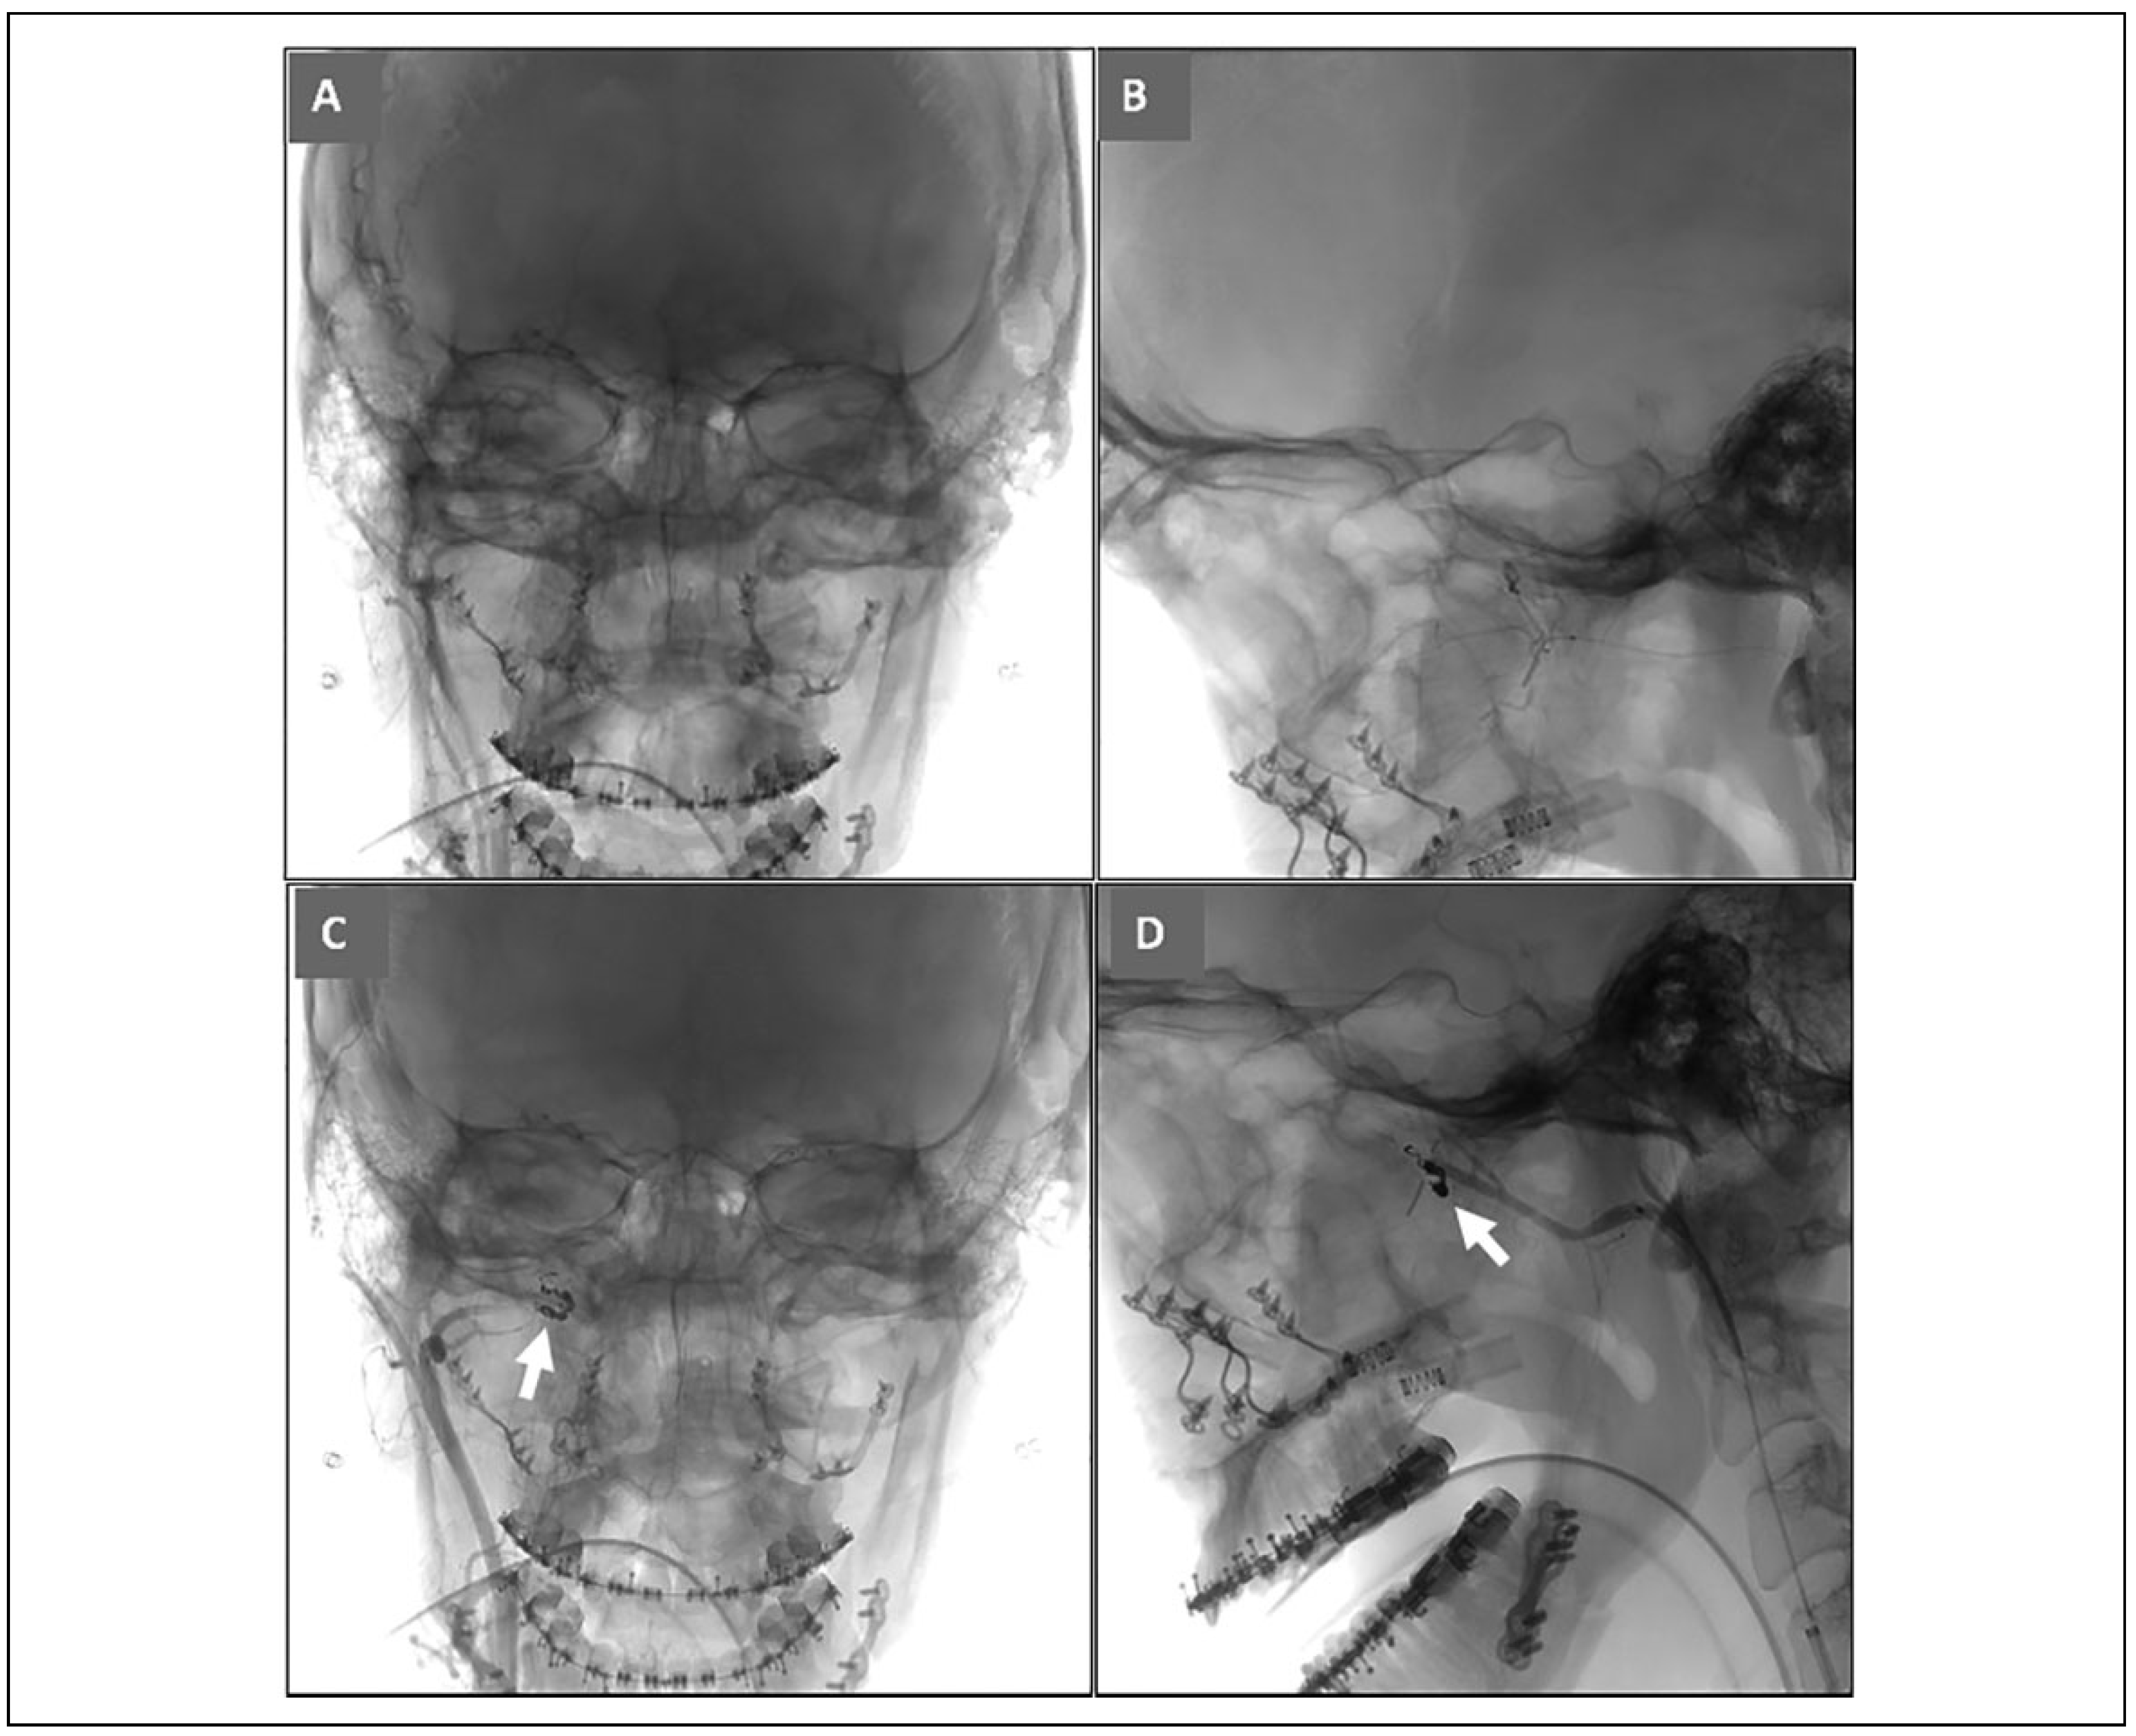

Case 3

A 24-year-old male with a history of unilateral cleft lip/ palate underwent single piece Le Fort 1 advancement/ impaction with bilateral sagittal split osteotomy and genioplasty. His surgical course was uneventful. Bilateral descending palatine arteries were not isolated or ligated during the Le Fort 1 disimpaction. He was discharged postoperative day 2. He returned to clinic 1 week later for adjustment of his postoperative rubber bands.

On postoperative day 11 he presented to the emergency room with an epistaxis episode that was initially controlled with placement of balloon rhinoplasty packing. He was discharged home for follow up and removal in clinic in 2 days, which resulted in recurrent bleeding that was controlled with more nasal packing. He was sent to the emergency room and neuro-interventional radiology was consulted. Emergent CT angiogram identified a ruptured pseudoaneurysm along the branch of the left internal maxillary artery (Figure 6). Hemostasis was achieved with coiling and nasal packing, and he was admitted for observation. His nasal packing was removed the next day which did not have any subsequent bleeding episodes.

Figure 6. Case 3; CT angiogram (axial view) showing ruptured pseudoaneurysm along the branch of the left internal maxillary artery (white arrow).